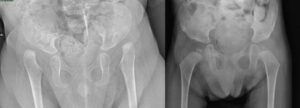

Knee surgery in arthrogryposis

Knee deformities are present in approximately 70% of children with classic arthrogryposis , presenting with flexion or extension deformities.

Knee flexion deformity in arthrogryposis

For flexion deformities, interventions may include:

- release of the soft tissues (hamstrings, posterior capsule) followed by possible progressive gypsotomies, i.e. progressive corrections in plaster using corrective stages

- distal femoral extension osteotomies

- gradual corrections with Ilizarov external fixator

- progressive corrections with anterior epiphysiodesis of the distal femur. These procedures have been used more frequently in recent years for these conditions, but their efficacy is still uncertain.

- In cases where cutaneous pterygia are present , collaboration with plastic surgeons is useful to treat both the skin component and the joint deformity component.

Knee extension deformity in arthrogryposis

For extension deformities (recurvatum, subluxation, dislocation), possible interventions include, after an adequate period of non-surgical treatment:

- quadricepsplasty using an inverted V-shaped anterior approach

- anterior capsulotomy with reduction of dislocation